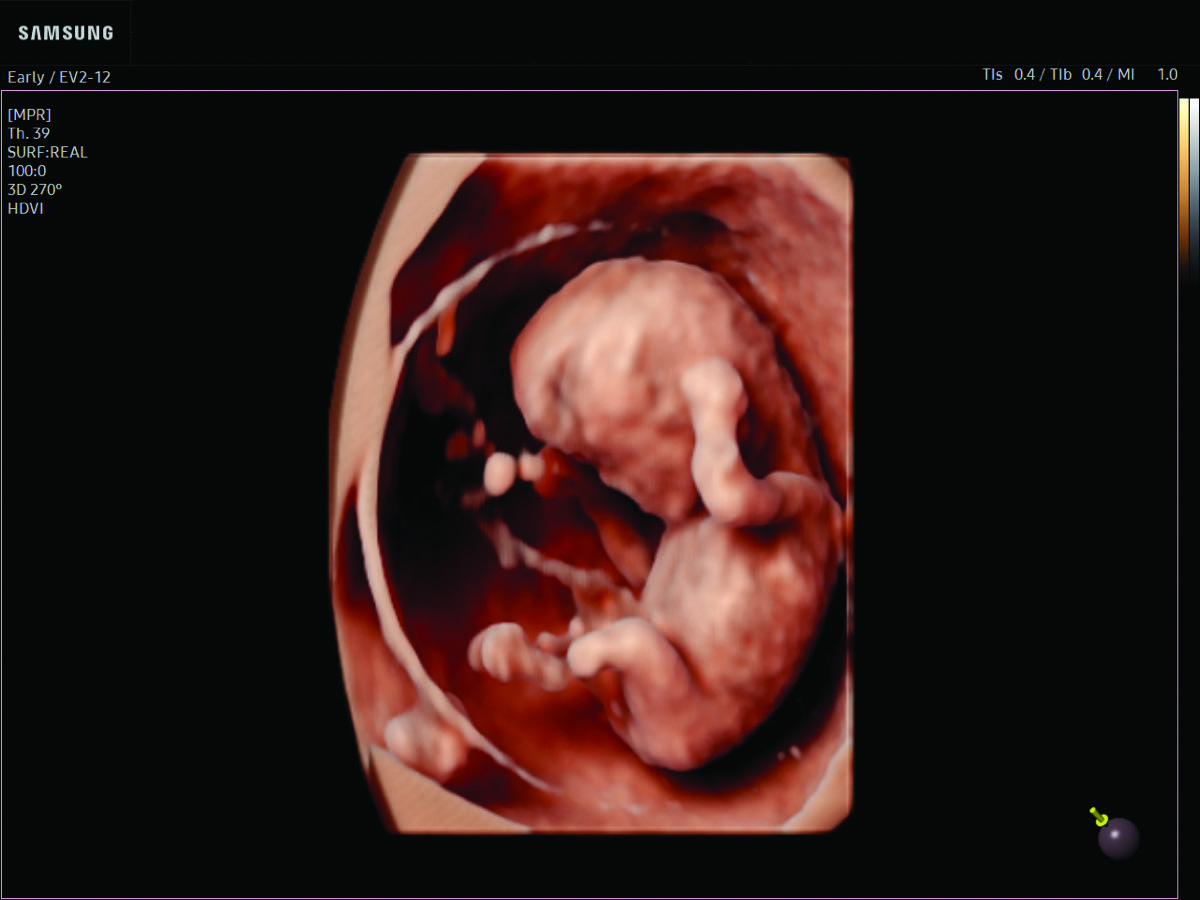

Comprehensive, advanced and expert MFM care for high-risk pregnancies

- Fetal anomalies